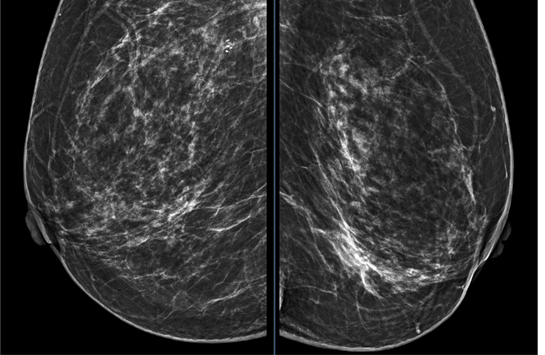

Không sử dụng những thuật ngữ chuyên môn phức tạp, chuyên gia đã phác họa một “bản đồ” rõ ràng, giúp mỗi người chủ động hơn trong việc bảo vệ lá phổi của mình. Sàng lọc sớm: Đừng đánh cược với số phận Tâm lý “trời kêu ai nấy dạ” khiến không ít người xem… Xem thêm

Theo các chuyên gia, tình trạng đa ung thư nguyên phát đồng thì (Synchronous Multiple Primary Malignancies) là khi hai hoặc nhiều khối u ác tính xuất hiện độc lập trong thời gian ngắn. Mặc dù ung thư phổi và ung thư tuyến tiền liệt đều là những bệnh lý thường gặp ở nam giới,… Xem thêm